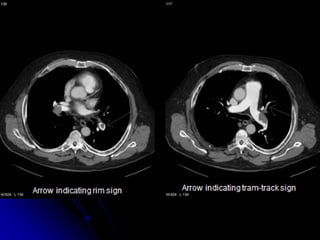

CTPA

Indications:

- Suspected PE

Contra-indications:

- Renal failure

- Pregnancy

- Allergy to radio-contrast

Procedure:

- Radioactive iodine administered IV

- CT scan performed

Multidetector helical CTPA

• First line modality

• Cover all chest with high spatial resolution in one breath

• Detect peripheral smaller emboli

• Detect other pathologies

• Detect RV strain (straightening or leftward bowing of IV

septum)

• Available

BUT

• Needs expert in reading

• Costy

• Not portable

• Radiation Exposure

• # in renal failure and contrast allergy